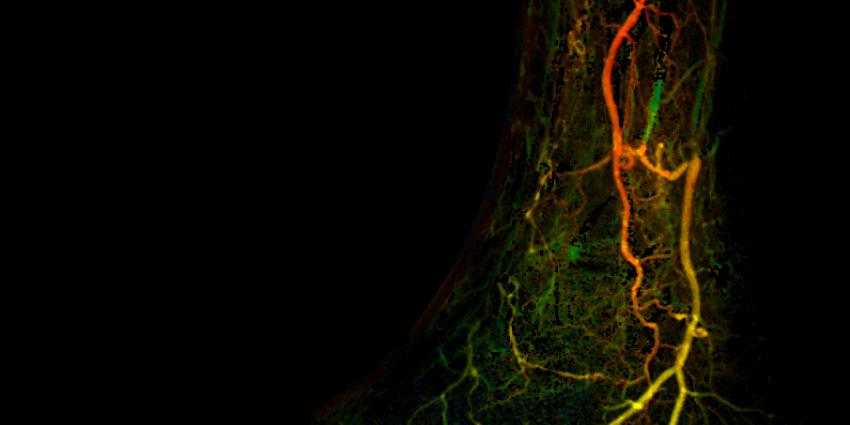

Foto: AMC

De organisaties zullen een nieuwe veelbelovende diagnostische techniek onderzoeken om bij de behandeling van diabetische voet en kritieke ischemie van het been direct de resultaten van een minimaal invasieve ingreep te kunnen beoordelen. Diabetische voet is een ernstige complicatie als gevolg van verminderde doorbloeding in het been, waarmee wereldwijd miljoenen diabetespatiënten te kampen hebben.

Amputatie is een van de ingrijpendste consequenties voor patiënten met diabetische voet. Op dit moment bestaat er geen diagnostische methode om direct het effect van angioplastiek te kunnen beoordelen. Angioplastiek is de behandeling van eerste keus om de bloedcirculatie in de voet te herstellen. Het effect kan pas maanden na de behandeling worden vastgesteld wanneer genezing is opgetreden of juist is uitgebleven. Daarom bestaat er een grote behoefte aan een nieuw diagnostisch hulpmiddel om het behandelresultaat te kunnen beoordelen en zo optimale nazorg te kunnen bieden. Het onderzoek gaat in de zomer van 2015 van start en de einduitkomsten ervan worden in 2017 verwacht.